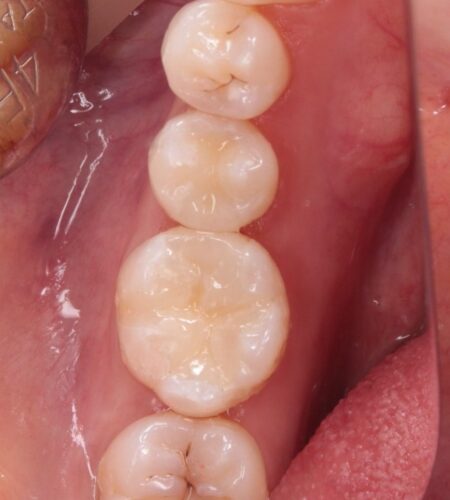

マイクロスコープ下で虫歯の取り残しがないよう注意しながら除去し、歯の神経にも感染は認められなかったので、セラミックでの審美的な回復を行いました。

とても喜んで頂けたので良かったです。